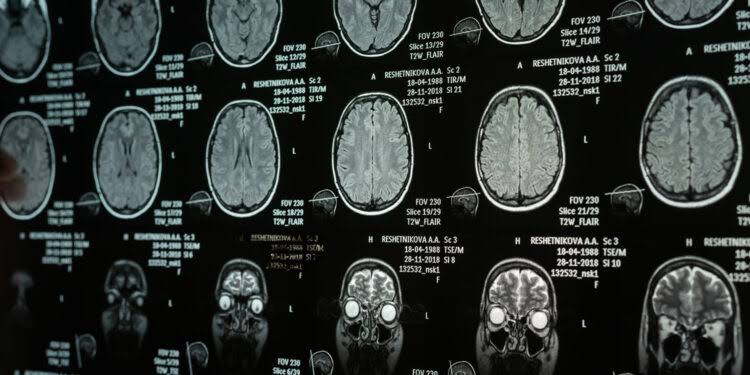

A new brain imaging study reveals how the physical structure of a region called the anterior insula...

A new brain imaging study reveals how the physical structure of a region called the anterior insula links narcissistic personality traits to the everyday...